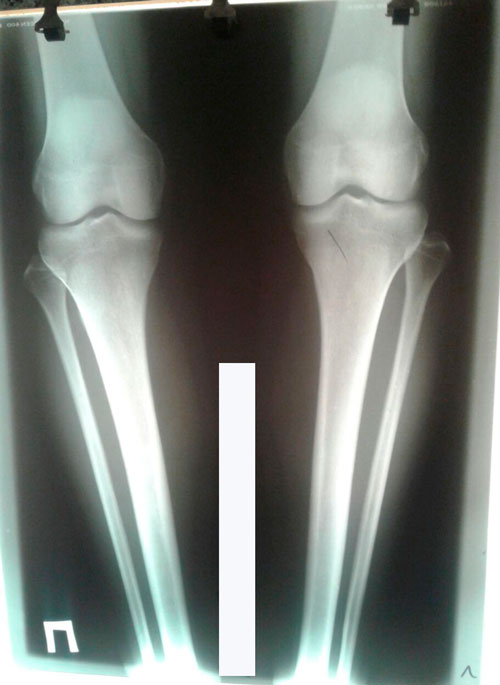

Исходник - 40 лет.

Дата операции 28 04.2017г.

Дата операции 28.04.2017г.

Дата снятия аппаратов 05.10.2017г.

Срок лечения 150 дней.

PS. из за личных обстоятельств, снятие аппаратов затянулось. Но пациентку это не беспокоило.